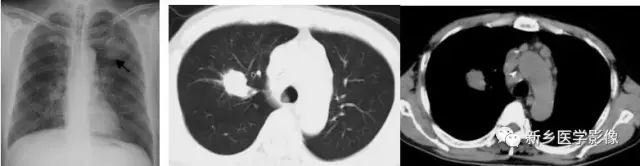

肺结核空洞CT图

a. 肺窗;b.纵隔窗,显示右上肺薄壁空洞(↑)

肺癌空洞CT图

a. 肺窗;b.纵隔窗,显示左上肺厚壁空洞(↑),内壁不规则,见壁结节

肺脓肿空洞CT图

a. 肺窗;b.纵隔窗,显示右上肺厚壁空洞(↑)周围见大片状模糊影